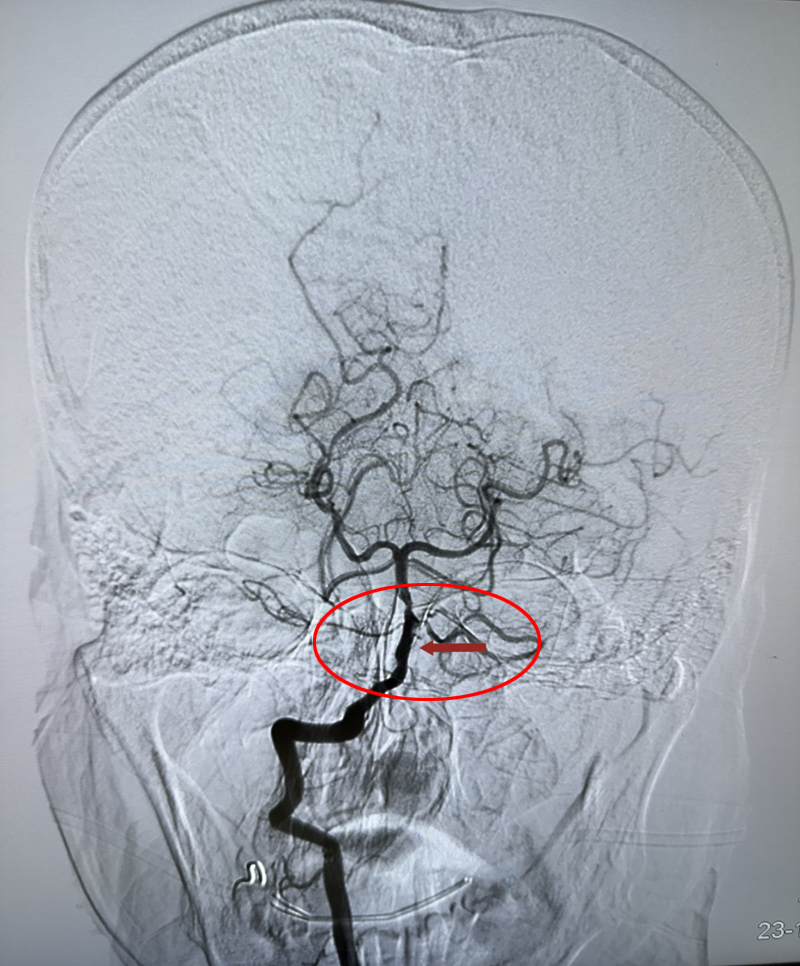

术后

11月2日晚上,60多岁的蒋女士从河北来北京探亲,刚下公交车后感到头晕不适,以为是晕车了就坐在路旁休息,没想到突然失去意识倒在了地上。家属赶紧拨打了急救电话,120急救车立即把蒋女士送到了潞河医院急诊抢救室。急诊神经内科肖淑英主治医师第一时间接诊后,对患者进行了查体,初步判断为急性脑血管病累及脑干,随时会有呼吸衰竭、心跳骤停的风险,情况十分紧急!于是立即启动卒中绿色通道,火速带着患者进行了头颅CT检查,考虑为椎基底动脉系统大动脉急性闭塞。二线值班医生车锋丽主任医师也迅速到达急诊室指挥抢救,同时联系神经介入组做好急诊介入手术准备。就在此时,蒋女士突然出现了血氧饱和度急剧下降,考虑呼吸中枢受累引起了中枢性呼吸衰竭,医生果断为她进行了气管插管接呼吸机辅助机械通气,并一路护送前往导管室进行急诊脑血管造影检查。神经内科副主任程哲带领手术团队已准备就绪,造影检查结果显示患者基底动脉急性闭塞,随即进行了基底动脉取栓手术,仅用时30分钟就成功完成了血管再通。蒋女士即刻恢复了意识,四肢也可以抬起活动了。由于抢救及时,蒋女士术后第二天就顺利拔除了气管插管,言语及四肢活动都恢复至正常状态,术后第五天顺利出院。